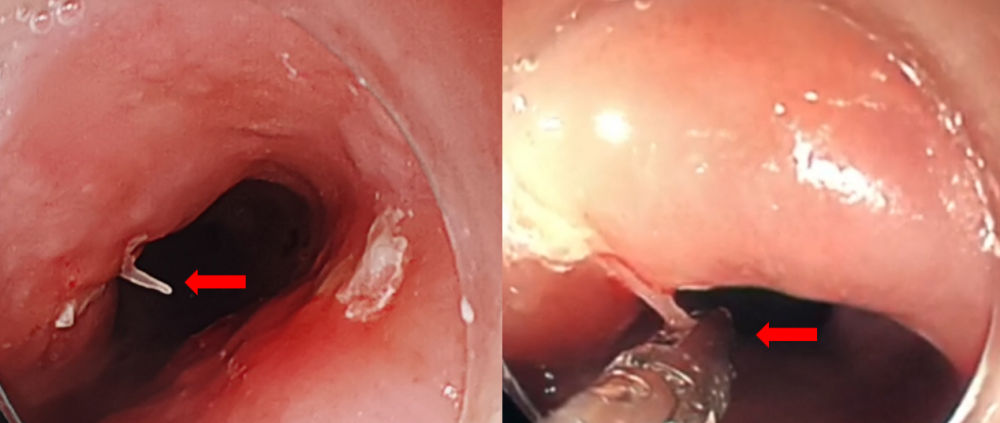

随后,梁婆婆在全麻下接受手术。广医二院微创介入科医生先将主动脉支架预先植入到位,接着,消化内科医生在内镜下找到鱼刺并将它夹住。接下来拔刺的步骤极为关键。因为一旦鱼刺拔出后,主动脉破口封堵不及时,有可能导致大出血。所以,拔出鱼刺和封堵支架的操作必须无缝衔接。手术团队密切配合,消化内科医生夹住鱼刺将其拔出,微创介入科医生马上释放支架将主动脉破口封堵住。一拔一封,只用了5秒钟!两个关键的手术步骤无缝衔接,大大地减少了术中的出血量。

左:内镜下可见鱼刺刺入食管;右:手术中医生用异物钳夹紧鱼刺。